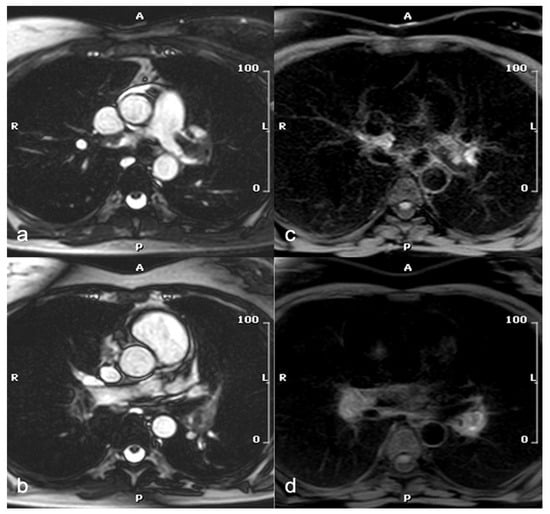

Recent studies have investigated the feasibility of diagnosing PE using non-contrast MRI, an approach that would be particularly beneficial for the pregnant population, as it avoids both radiation exposure and the administration of contrast media. The balanced steady-state free precession (SSFP) sequence has proven to be of greatest interest, producing predominantly T2-weighted (T2w) contrasts, enabling the inherent distinction between embolic material and blood in patent pulmonary vessels without the need of contrast media [49] (Figure 1).

Figure 1.

A 47-year-old woman at week 20 of pregnancy with shortness of breath and D-dimer elevation. Axial SSFP images show left and right main pulmonary artery filling defects (a,b), consistent with acute pulmonary embolism, confirmed by T1-w images with blood and fat saturation (c,d). SSFP: steady-state free precession.

Additionally, the usefulness of a T1-weighted (T1w) sequence with fat and blood suppression has been investigated for visualizing embolic material. As blood clots, it goes through distinct stages that correspond to the oxygenation state of hemoglobin within red cells. During one of these stages, methemoglobin forms and acts as an endogenous contrast agent, showing a high signal on T1w sequences (Figure 1). The suppression of adipose tissue and blood signal increases contrast with the hyperintense thrombo-embolic component, facilitating clot detection. This technique shows potential for identifying fresh thrombus in cases of deep vein thrombosis and PE [57]. Furthermore, the feasibility of diffusion-weighted imaging (DWI) has been assessed for PE detection in free-breathing humans. DWI has demonstrated high sensitivity for detecting PE but is limited by poor specificity. It may serve as a useful “eye-catcher”, highlighting arteries that require closer examination. This could potentially enhance diagnostic quality, particularly at the subsegmental level, and reduce reading time [58]. MRI in the context of pulmonary embolism can also provide functional and prognostic information, with cine-SSFP sequences identifying right ventricular pressure overload, evidenced by reduced ejection fraction, increased ventricular volumes, and interventricular septal flattening (Figure 2) [59].

Figure 2.

A 47-year-old woman with shortness of breath and D-dimer elevation at week 20 of pregnancy. Short-axis SSFP image (a) shows interventricular septum flattening in mid-systolic phase due to increased intracavitary pressure in the right ventricle. The four-chamber SSFP image (b) demonstrates right ventricular enlargement compared to the left ventricle. SSFP: steady-state free precession.